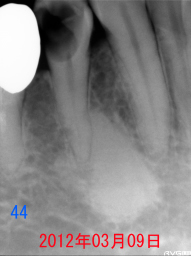

それから3年7ヶ月後、歯がかけたと来院。 ←同部のレントゲン写真 虫歯が神経まで進行しているように見えますが、 |

| 無麻酔下で完全に虫歯に除去しても 露髄せず、神経が第二象牙質で完全に 覆われています。 |

上記のレントゲン写真。 神経もとらずに、治療が出来ます。 |